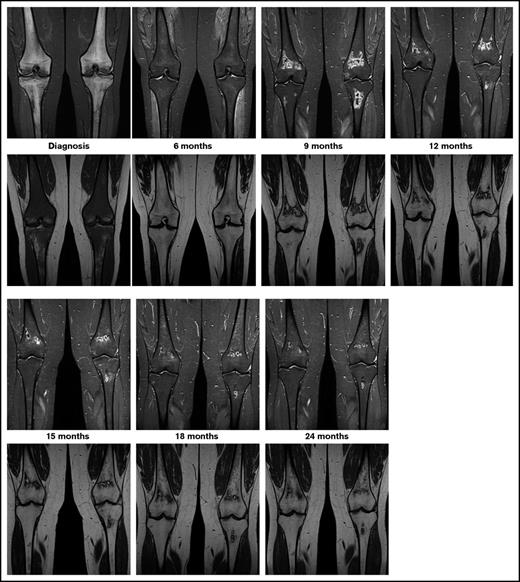

The currently ongoing OPAL trial (osteonecrosis in pediatric patients with acute lymphoblastic leukemia and lymphoblastic lymphoma)6 is addressing these questions via serial MRI screening of adolescents with newly diagnosed ALL or lymphoblastic lymphoma. Preliminary results of this trial highlight the unpredictable course of asymptomatic MRI lesions, ranging from spontaneous regression via subclinical persistence to rapid progression. Epiphyseal disease tends to progress rapidly. In contrast to this, as seen in Figure 1, metaphyseal/diaphyseal disease does not commonly cause any harm, and it may even disappear, since it is far away from the joint line. Thus, ON studies in children with ALL should focus on the lesions located in the epiphyseal areas near the joint line, where the risk of joint collapse increases.

Exemplary patient from the OPAL trial. On coronal images of knees, short tau inversion recovery images (top row) show diffuse hyperintense inhomogeneous signals, and T1-weighted images (bottom row) show diffuse hypointense signals revealing extensive leukemic infiltration of bone at diagnosis. At the 6-month follow-up examination, the hyperintense signal in short tau inversion recovery decreased and the hypointense signal in T1 increased toward normal appearance. At 9 months into treatment, MRI shows asymptomatic lesions in the metaphyses, which shows spontaneous regression beginning at 12 months into treatment.